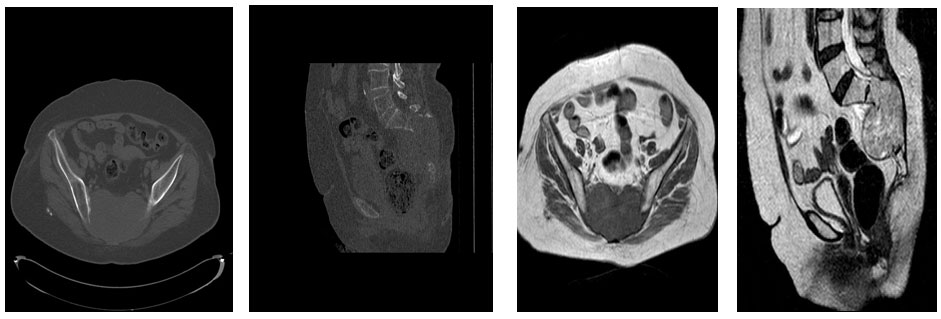

Ameliyat Öncesi: Tomografide ve MR’da sakrumda kemik harabiyeti ve rektuma dayanmış tümör dokusu görülmekte